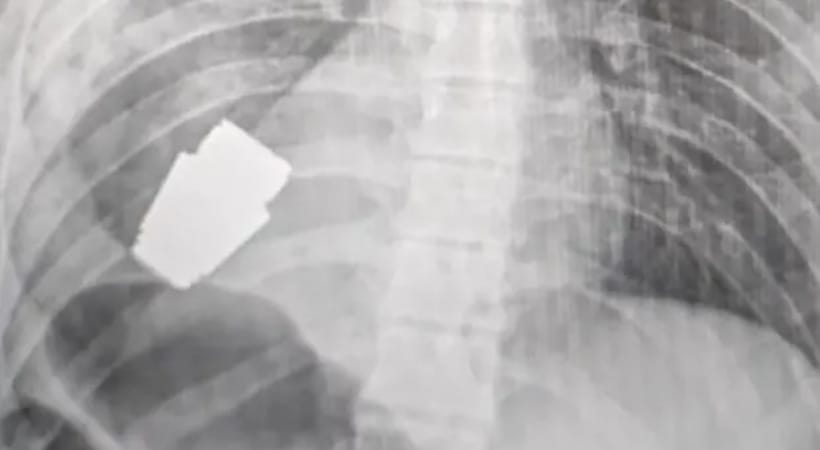

വിജയകരമായ ഒരു അസാധാരണ ശസ്ത്രക്രിയയിലൂടെ യുക്രൈനിയന്‍ സൈനികന്റെ നെഞ്ചില്‍ നിന്നും ഒരു ഗ്രനേഡ് പൊട്ടാതെ പുറത്തെടുത്തു. ഏത് നിമിഷവും പൊട്ടിത്തെറിക്കാമെന്ന നിലയിലുള്ള ഗ്രനേഡ് സ്വന്തം ഹൃദയത്തിന് താഴെ പേറിയാണ് സൈനികന്‍ ആശുപത്രിയിലെത്തിയത്. യുക്രൈന്‍ തലസ്ഥാനമായ കീവിലെ സൈനിക ആശുപത്രിയില്‍ നടന്ന അത്യന്തം അപകടകരമായ ശസ്ത്രക്രിയയ്‌ക്കൊടുവില്‍ സൈനികന്‍ ജീവിതത്തിലേക്ക് മടങ്ങി വരികയായിരുന്നു.

ഗ്രനേഡ് പൊട്ടാന്‍ സാധ്യത ഉണ്ടായിരുന്നതിനാല്‍ രക്തസ്രാവം നിയന്ത്രിക്കുന്നതിനുള്ള ഇലക്ട്രോ കോഗുലേഷന്‍ പോലും ഉപയോഗിക്കാതെയാണ് ശസ്ത്രക്രിയ നടത്തിയത്. സൈനിക ആശുപത്രിയിലെ വിദഗ്ധരുടെ സൂക്ഷ്മതയും കരുതലുമാണ് സൈനികനെ ജീവിതത്തിലേക്ക് മടക്കിക്കൊണ്ടുവന്നത്.

മെഡിക്കല്‍ പാഠപുസ്തകങ്ങളില്‍ വരും വര്‍ഷങ്ങളില്‍ ഇടംപിടിക്കുന്ന തരത്തിലുള്ള അവിശ്വസനീയമായ ശസ്ത്രക്രിയയാണ് സൈനിക ആശുപത്രിയിലെ വിദഗ്ധര്‍ നടത്തിയതെന്ന് യുക്രൈന്‍ പ്രതിരോധമന്ത്രി ഹന്ന മാലിയാര്‍ പറഞ്ഞു. സൈനികന്റെ ശരീരത്തില്‍ നിന്ന് വിഒജി ഗ്രനേജ് വിജയകരമായി നീക്കം ചെയ്തുവെന്ന വാര്‍ത്ത മന്ത്രി തന്നെയാണ് പുറത്തുവിട്ടത്. ആയുധം നിര്‍വീര്യമാക്കിയിട്ടുണ്ടെന്നും മന്ത്രി വ്യക്തമാക്കി.